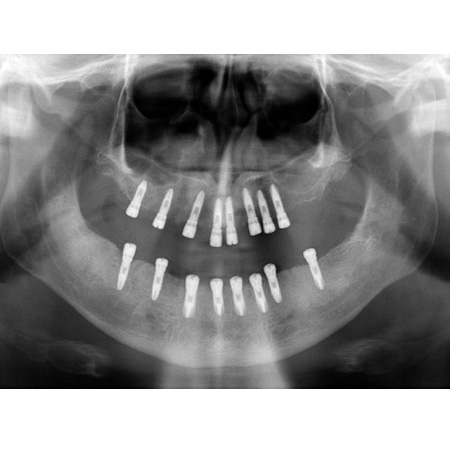

Nº5 CIRUGIA DE IMPLANTES GUIADA POR ORDENADOR

Varón de 55 años desdentado completo, presentaremos la resolución del caso próximamente.